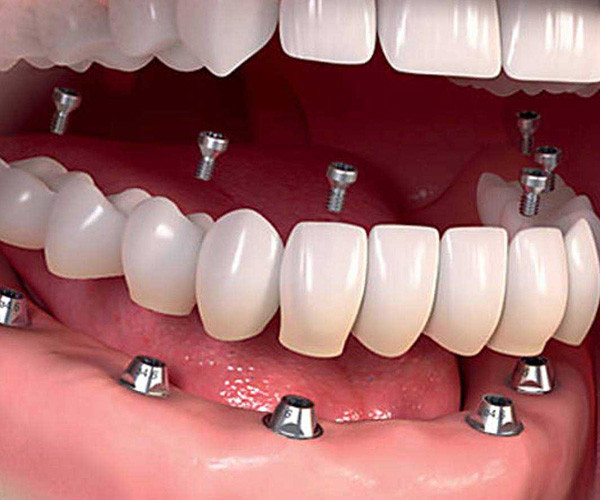

Yes it is possible to get a whole new set of teeth

Struggling with dental issues can be painful and stressful. If you’ve been dealing with tooth loss and wish you could have a new set of teeth, implant surgery can make this happen.

Dental implants have been in use for decades now and have an excellent track record. These teeth act just like your regular teeth so you have no food restrictions and they don’t need a complicated maintenance routine, just good oral hygiene practices and routine check-ups will suffice to keep them in good shape.

Can I have all my teeth pulled and get implants?

Yes, it is possible to get a whole new set of teeth. This is often the route chosen by those who have been dealing with dental distress for years.

Permanent dental implants are made with metals like titanium or zirconia. They are embedded well into the gum line and act just like the roots of your teeth. Replacement teeth are then affixed onto these implants. Dental implants can last a lifetime and are considered to be a permanent solution for tooth loss. All-on-four and all-on-six dental implant surgeries can be done to give you a new set of teeth in just one jaw or your entire mouthful of teeth.

The experienced dentists at Dental Artistry are able to insert implants in your jaw and fix in a whole new set of teeth that are anchored firmly by the implants. Not only are these a permanent, more efficient solution but they also prevent bone loss or erosion and the consequent sagging of the face often associated with dentures.

How many implants are needed for a full mouth?

Dental Artistry offers the option of giving you a full set of teeth with just four sets of implants. This surgical procedure is called all on four. One implant can hold in place multiple teeth. Sometimes your dentist may recommend that you have six implants instead of six, this is called the all on six procedure. Your dentist will advise how many implants are best for your needs.